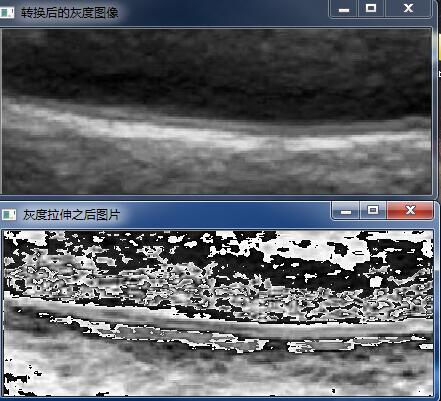

1)灰度拉伸

灰度拉伸和也属于灰度的线性变换,灰度拉伸和灰度线性变换相似。不同之处在于它是分段线性变换。表达式如下:

其中,x1和x2是分段函数的转折点。这里的转折点,从直方图上看就是从左边以及从右边看两个转折点(也就是增到减,或者减到增那个点)这里我们选择(20,550),(200,70)

void HistD(cv::Mat &image){int table[256] = { 0 };int nr = image.rows;int nc =image.cols*image.channels();int x1 = 30, y1 = 550, x2 = 200, y2 = 70;for(int j =0;j<nr;j++){uchar * data =image.ptr<uchar>(j);for(int i=0;i<nc;i++){if (data[i]<x1){data[i] = y1/x1 *data[i];}else if (data[i]<x2 ){data[i] = (y2-y1)/(x2-x1)*(data[i] -x1)+y1;}else{data[i] = (255-y2)/(255-x2)*(data[i] -x2)+y2;}}}imshow("灰度拉伸之后图片", image);

}

这个和论文中的有出入,我对于灰度拉伸的理解是着两个转折点横坐标的范围转换为纵坐标饿范围,在直方图上可以很清楚的看见变化,但是从实际效果来说的话可能处理图像达不到预期的效果,这里还有待研究。